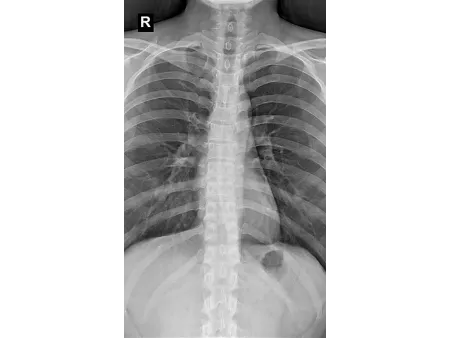

Este sistema radiográfico de doble columna está diseñado especialmente para salas DR, ofreciendo una estructura robusta y versátil que facilita el posicionamiento en distintos ángulos y alturas. Es ideal para realizar estudios detallados de cráneo, tórax, abdomen, columna lumbar y extremidades, y permite trabajar con proyecciones PA, laterales y otras imágenes clínicas estáticas con alto nivel de precisión.

Integra una pantalla táctil de 7 pulgadas que permite gestionar de forma intuitiva las funciones del equipo, junto con un sistema avanzado de adquisición digital que proporciona imágenes nítidas, consistentes y de alta resolución, adaptándose a los requerimientos de diagnóstico más exigentes. Está disponible en dos modelos: SHO-DDX03 y SHO-DDX04, ambos con varias configuraciones de potencia para ajustarse a distintos flujos de trabajo: 20 kW / 200 mA, 20 kW / 320 mA, 32 kW / 400 mA, 40 kW / 500 mA, 50 kW / 630 mA. Para aplicaciones clínicas más complejas que requieren mayor capacidad, el modelo SHO-DDX04 alcanza una potencia de hasta 65 kW / 800 mA, garantizando imágenes de alta calidad incluso en estudios que demandan una penetración más profunda o un nivel superior de detalle.